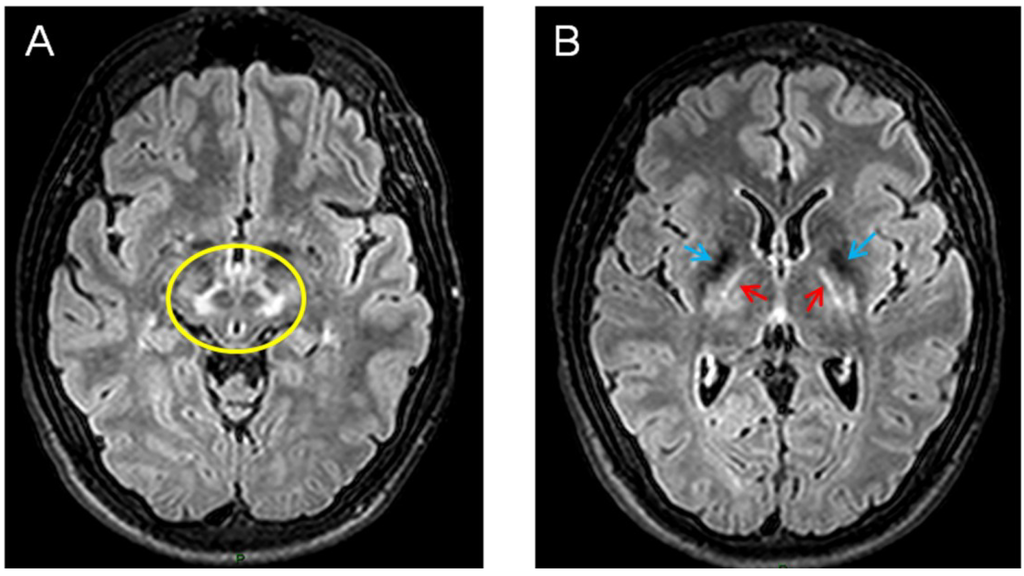

Figure 2. Brain MRI (axial flair images) showing zones of impaired signal at the level of mesencephalon (A) and thalami (B) in a 21-year-old patient presenting Wilson’s disease. In the left panel, note the relative sparing of red nuclei and part of pars reticulata (giving a typical aspect called the “Panda sign”). In the right panel, the simultaneous hyposignals of basal ganglia (blue arrows) and the hypersignals in thalamic nuclei and internal capsule (red arrows) are very suggestive.

Wilson’s disease (WD) is an autosomal recessive disease involving the ATP7B gene. This causes deficits not only for the excretion of copper into the bile, but also in terms of the binding of copper to ceruloplasmin. Patients exhibit, in particular, deficits of the nervous system (with both neurological and psychiatric signs) and the liver. The Kayser–Fleischer ring (brown discoloration of the cornea) is very suggestive. Whereas the juvenile form is mainly associated with liver symptoms, the adult presentation tends to manifest mainly with neurological deficits [60]. Brain MRI shows areas of increased signals (Figure 2).